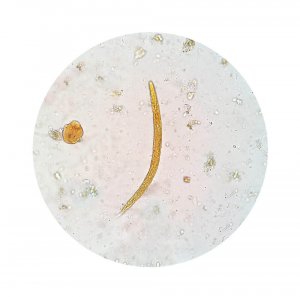

Denne infeksjonen kan lett oppdages ved en avføringsprøve. Dette vil vise om det er aktive amøber eller cyster.

Den virkelige årsaken til amøbedysentri er en mikroorganisme kalt Entamoeba histolytica.

Denne organismen sprer seg rundt i kroppen gjennom ekskrementer og overføres til andre når den smitter mat eller vann. Den påvirker slimet i tarmene, spesielt i tykktarmen.